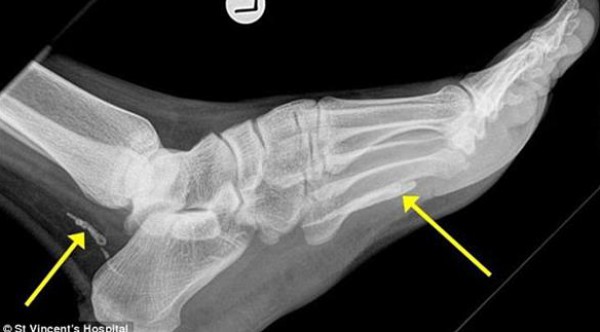

شعر هذا السوداني (38 عاماً) الذي توجه إلى ملبورن للاستقرار هناك، بتورم قدمه وكاحله بعد آلام استمرت معه لعام تقريباً، فزار الطبيب، ليظهر للأخير في الأشعة السينية التي أجراها المريض وجود دودة طولها متر، بحسب صحيفة دايلي ميل البريطانية.

قام الأطباء بتحليل الدودة، فتبين أنها كانت مستقرة في منطقتي الكاحل والقدم على شكل قطعتين لولبيتين لأكثر من 4 سنوات، مشيرين إلى أنها ماتت بعدما تغذت على لحم القدم وبدأت في التحلل داخل جسم الرجل، محدثة له تورماً وقروحاً.